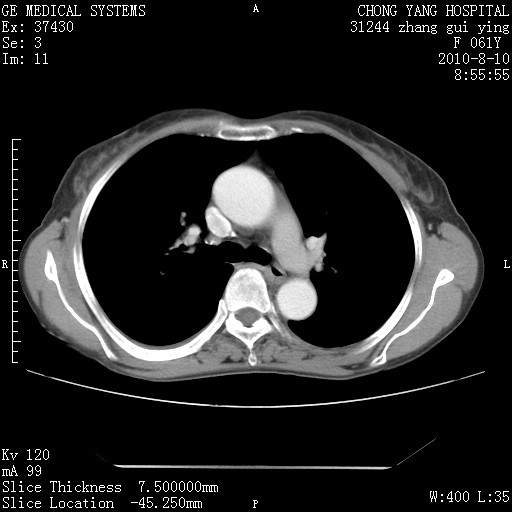

1、支持考虑右侧中央型肺癌伴右肺中叶节段性不张及下叶支气管黏液痰栓    2、左肺上叶舌段感染。

支持3楼意见,还要考虑:纵隔及肺门淋巴结转移、右侧少量胸腔积液。

确切的说:1:右肺下叶中心型肺癌侵及中叶支气管并中叶不张,纵膈淋巴结转移。2:左肺舌叶炎症。3:右侧胸腔少量积液

块影平扫32hu,动静脉期62-70hu.